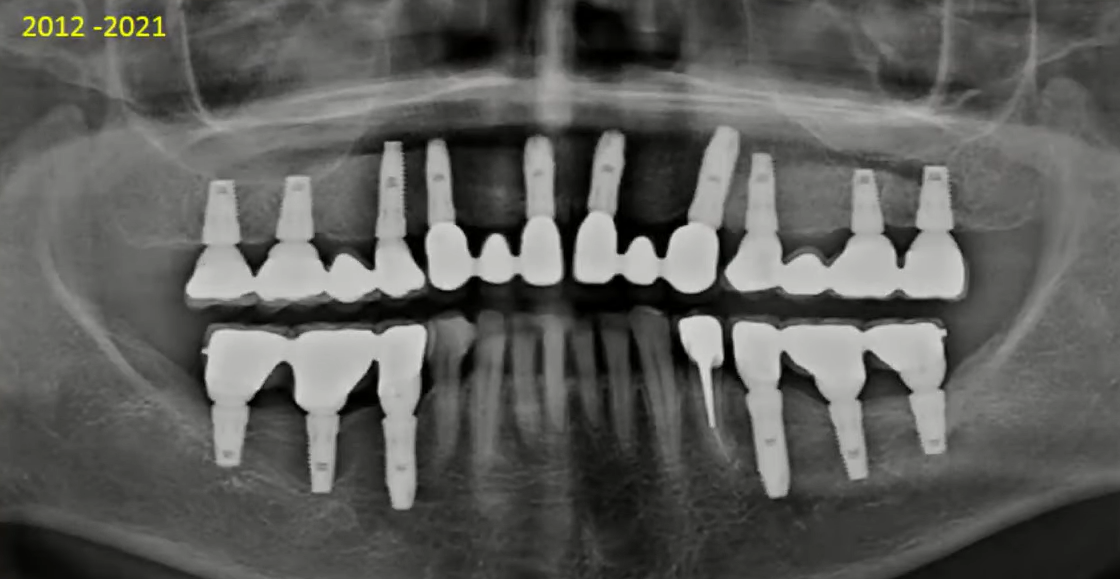

The following photo shows a restoration 9 years post-op, and the bone level around the implants has remained virtually unchanged. Several factors were at play here:

- Correct load distribution: The upper jaw is divided into 4 bridges and has a sufficient number of implants (10 units).

- Sufficient bone volume between the implants: A distance of at least 3 mm ensures good blood supply to the bone tissue, which is crucial for long-term stability, as confirmed by this image.

- The right choice of implant design: The implants are well integrated, and this restoration can last for many more years without significant changes.

An example of a successful restoration with minimal bone loss around the implants 9 years after implant placement. YouTube / Dr. Kamil Khabiev / Dental Guru Academy